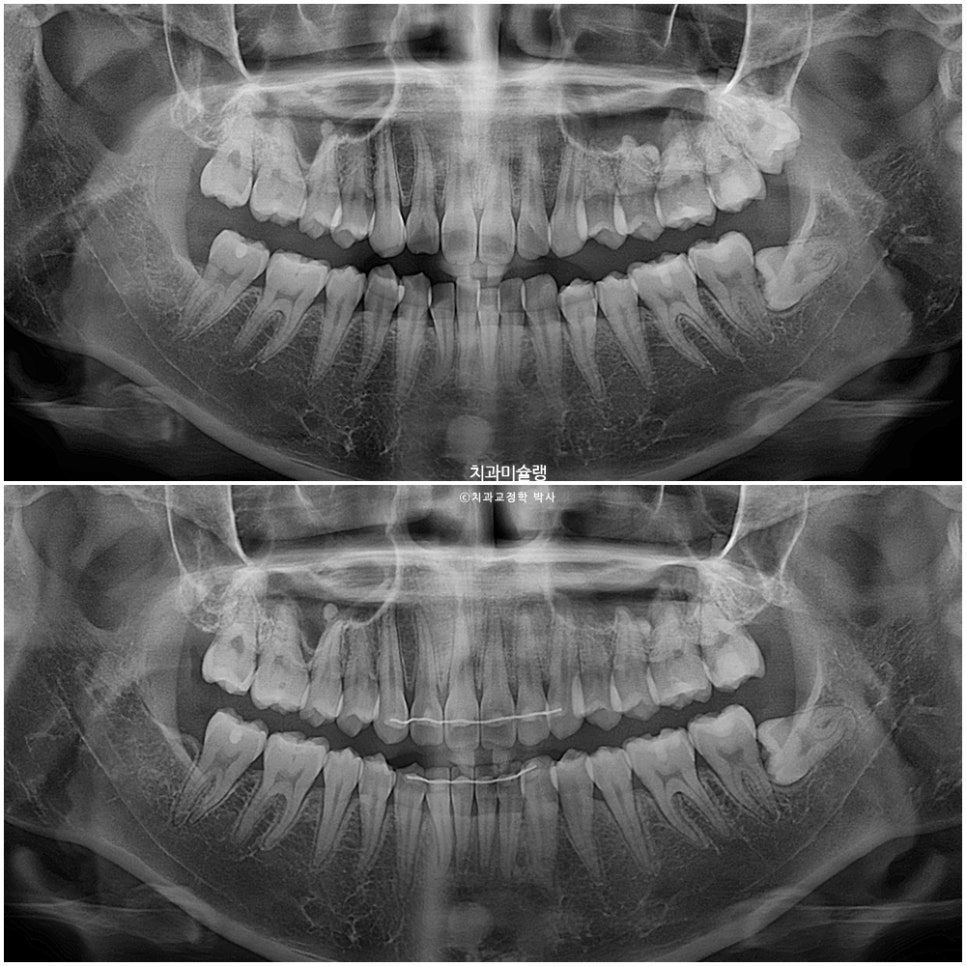

치료 결과 분석

교정기간 내 치근흡수는 없으며 치근평행도는 양호합니다.

작은어금니 회전까지 완벽 개선되었습니다.

전체 치료기간은 9개월, 재제작은 1회 했습니다.